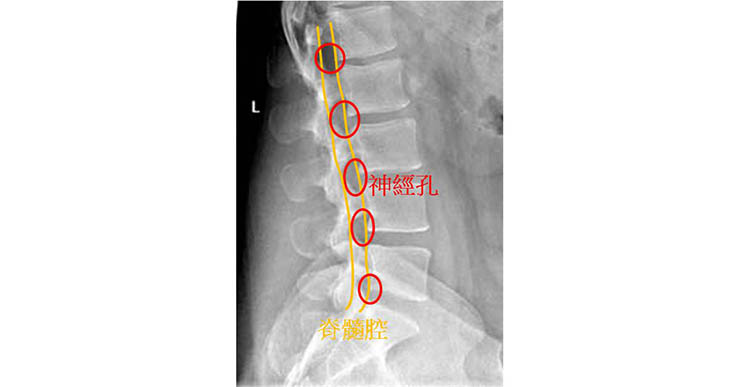

脊髓和神經根分別長在如圖示的地方,於是乎,除了這附近以外的骨刺基本上是不會造成影響的。 (如下圖)

1. 位置長在神經孔(神經根走出來的地方)正旁邊,影像要明顯看到神經孔有狹窄的現象。